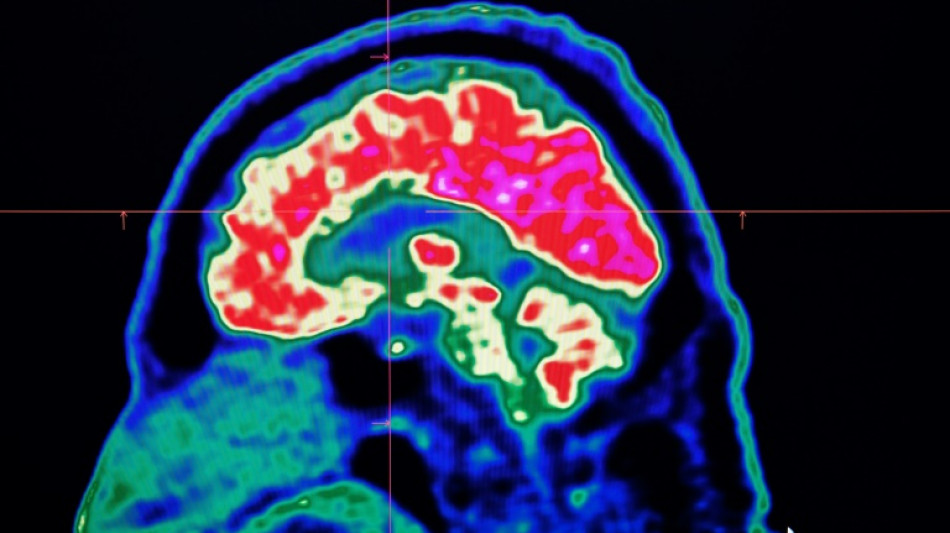

Conditions affecting the nervous system -- such as strokes, migraines and dementia -- have surged past heart disease to become the leading cause of ill health worldwide, a major new analysis said on Friday.

More than 3.4 billion people -- 43 percent of the global population -- experienced a neurological condition in 2021, far more than had previously been thought, the analysis found.

The researchers looked at how 37 different neurological conditions affected ill health, disability and premature death across 204 countries and territories from 1990 to 2021.